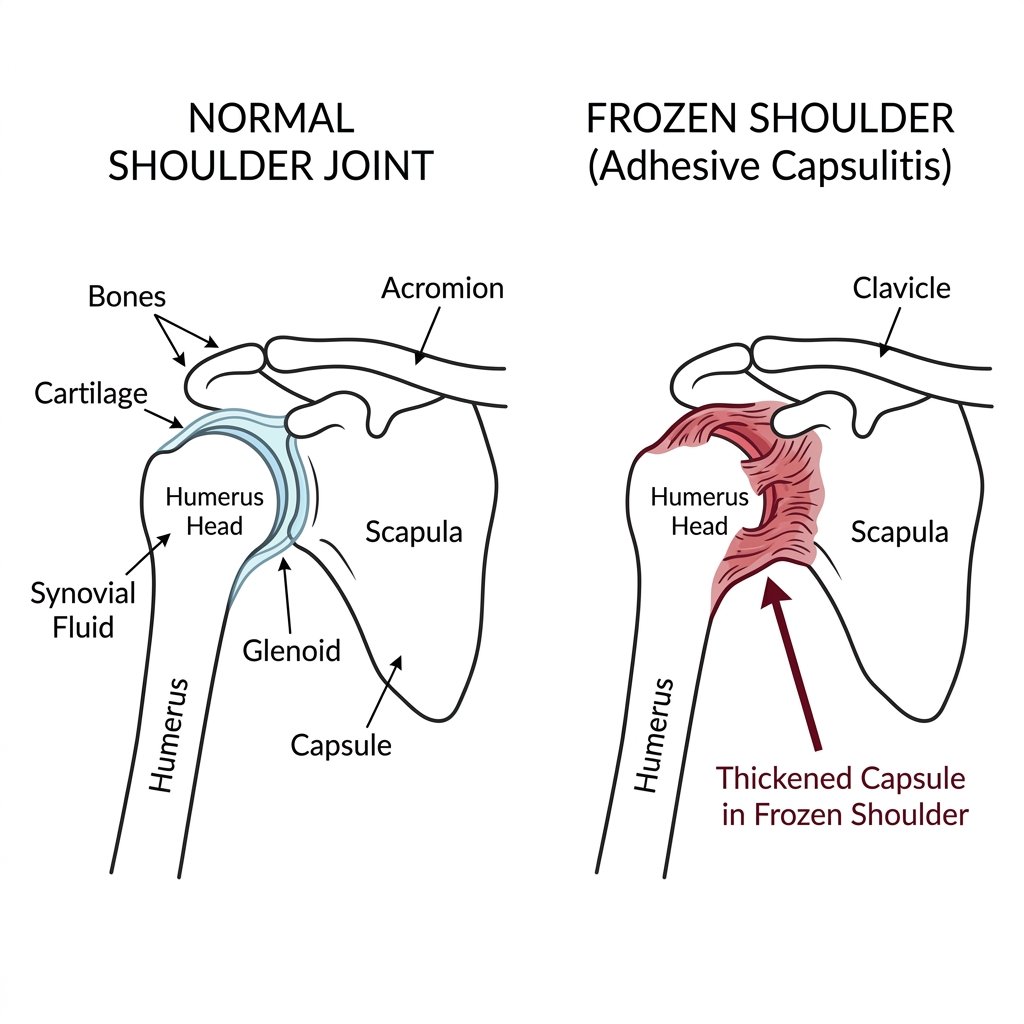

1 Essential Frozen Shoulder Treatment London Guide | LSRI

Frozen shoulder treatment london— medically known as adhesive capsulitis — is one of the most common and most misunderstood shoulder...